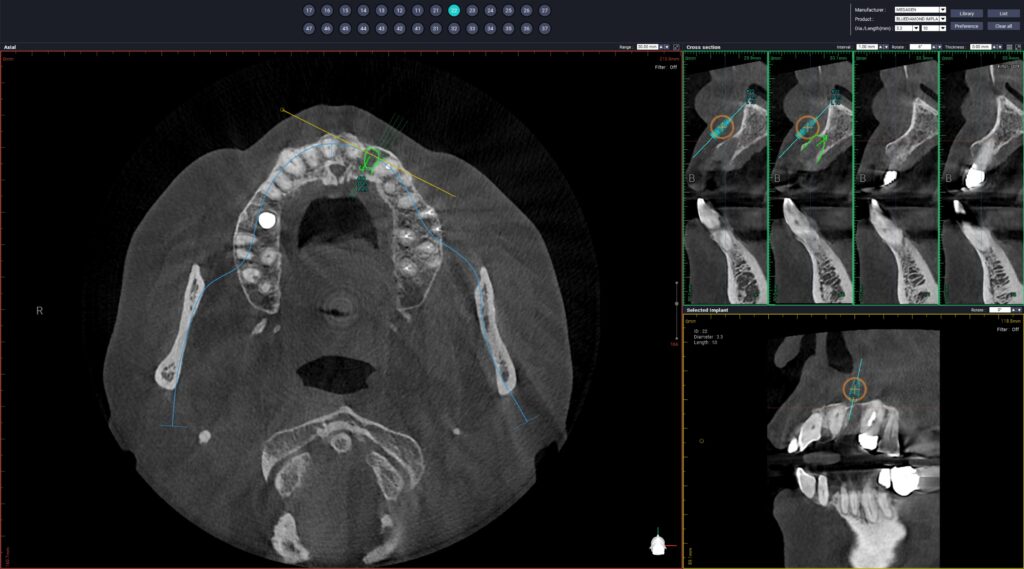

진행하기 전 CT 촬영을 통해 정밀한 진단을 바탕으로

치료를 계획하였습니다.

뼈이식 후 임플란트 식립을 진행한 모습입니다.

앞니 부위 임플란트는

특히 위치와 각도, 잇몸선과의 조화가

결과에 큰 영향을 주는데요.

심미적인 요소를 세밀하게 반영해야 하기 때문에

식립 전 계획 과정이 더욱 중요하여

발치 직후 임플란트를 식립하는

즉시 식립의 경우에도 디지털 분석을 통해

보철물 형태까지 함께 예측하는 접근이 활용되고 있습니다.